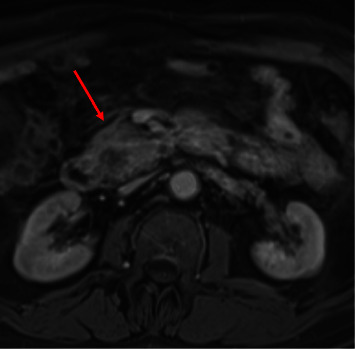

髓系肉瘤(MS)是急性髓系白血病(AML)的髓外表现,通常发生在淋巴结、皮肤、软组织和骨骼等部位。在胰腺中的表现更为罕见,自1987年以来,文献报道的病例不足20例。尽管 MS 很罕见,但在鉴别诊断引起阻塞性黄疸的软组织肿块时应考虑 MS,尤其是当患者患有已知的血液病时。已知胰腺多发性硬化的孤立病例可发展为急性髓细胞性白血病;因此,将多发性硬化与胰腺癌或胰腺炎等更常见的诊断相鉴别至关重要。这是一例 70 岁男性因胰腺多发性硬化继发症状性梗阻性黄疸的病例,最终需要通过内镜超声(EUS)和内镜逆行胰胆管造影(ERCP)进行诊断和治疗。该报告还全面回顾了以往类似胰腺多发性硬化症的临床表现、管理和治疗的病例报告。

Myeloid sarcoma (MS) is an extramedullary manifestation of acute myeloid leukemia (AML) and commonly occurs in sites such as the lymph nodes, skin, soft tissues, and bone. It more rarely manifests in the pancreas, with less than 20 cases reported in the literature since 1987. Despite its rarity, MS should be considered in the differential diagnosis of a soft tissue mass causing obstructive jaundice, especially if the patient has a known hematologic disease. Isolated cases of pancreatic MS have been known to progress to AML; therefore, it is crucial to differentiate MS from more common diagnoses, such as pancreatic cancer or pancreatitis. This is a case of a 70-year-old male with symptomatic obstructive jaundice secondary to pancreatic MS, ultimately requiring endoscopic ultrasound (EUS) and endoscopic retrograde cholangiopancreatography (ERCP) for diagnosis and management. Also included is a comprehensive review of previous case reports with similar clinical presentations, management, and treatment of pancreatic MS.